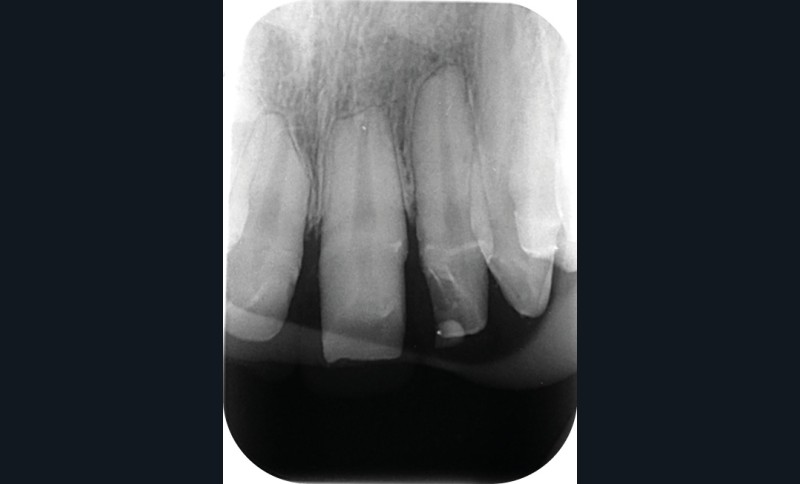

Une patiente âgée de 12 ans a été adressée au cabinet pour « une prise en charge complète sur le long terme » par son praticien traitant. Elle était accompagnée par sa mère. Elle présentait des couronnes transitoires en résine sur le secteur incisivo-canin au maxillaire ainsi que les premières prémolaires, des coiffes pédodontiques métalliques sur les premières molaires, une absence totale d’émail sur l’ensemble de la denture, à l’exclusion des bords libres des incisives mandibulaires (fig. 1 à 3). Le bloc incisivo-canin mandibulaire avait bénéficié de traitements radiculaires (fig. 4). Les incisives maxillaires présentaient des rhizalyses d’une importance significative (fig. 5 et 6). La patiente se plaignait d’hypersensibilités à la mastication et au brossage, la demande esthétique était forte.